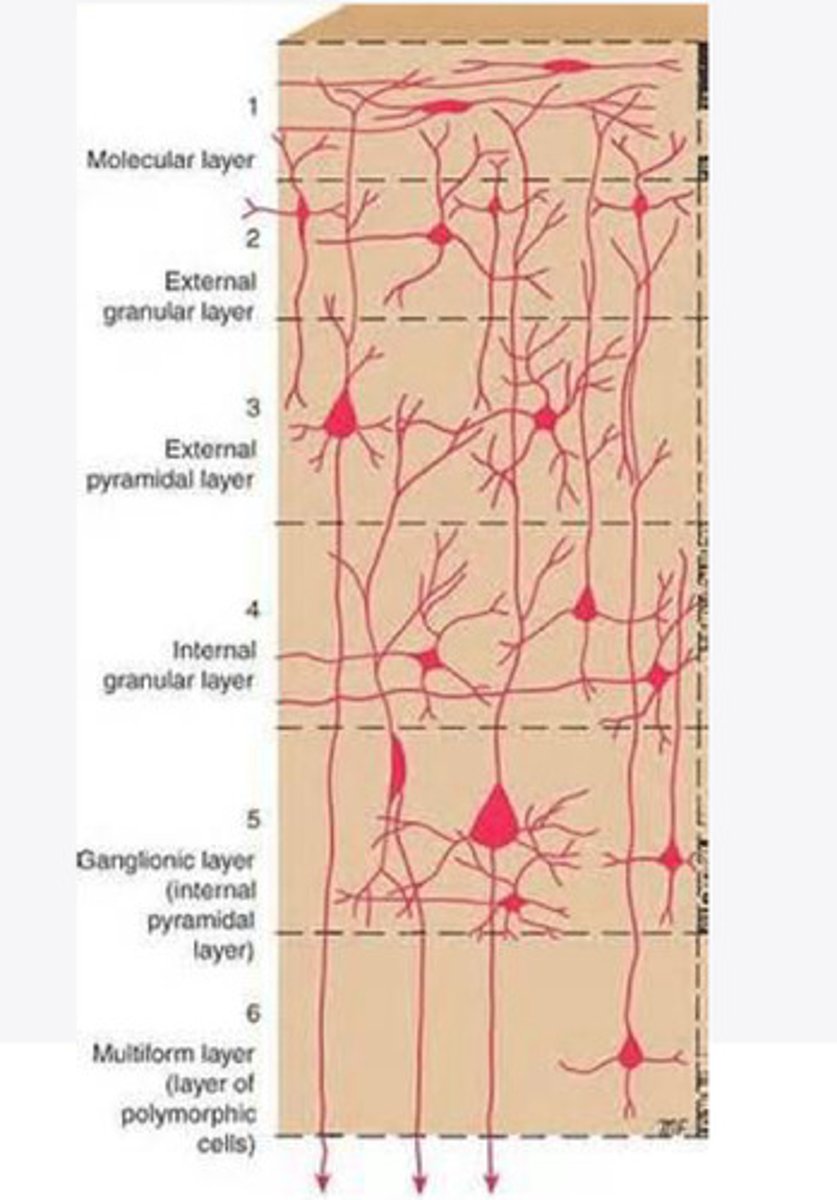

divided into 6 distinct layers, due to varying densities of cell body types within each layer

The cortex of the brain is divided into how many layers? Why is it divided into layers?

Layers of the cortex of the brain pic

2 and 4

What are the layers of the cortex that are associated with input?

3 and 5

What are the layers of the cortex that are associated with output?

molecular layer

What is the name of Layer 1 of the cortex of the brain?

very few cells

Does Layer 1 of the cortex have a lot or few cells?

receives dendrites from internal layers so it may actually function as a coordinating center where layers can communicate action

What does Layer 1 of the cortex do?

1

Every layer sends densities to Layer ____?

1

What layer serves as the "water cooler" of the brain?

external granular layer

What is the name for layer 2 of the cortex of the brain?

receives input from other cortical regions

What is the function of Layer 2 of the Cortex of the brain?

Stellate

What type of cells (stellate/pyramidal) would be most concentrated in Layer 2?

external pyramidal layer

What is the name for layer 3 of the cortex of the brain?

sends output to the other cortical layers

What is the function of Layer 3 of the cortex of the brain?

pyramidal

What type of cells (stellate/pyramidal) would be most concentrated in Layer 3 of the brain?

Layers 2 and 3

What layers are associated with association and commissural fibers?

Layer 3 - axons of cell bodies

Layer 2 - synapse into target areas in Layer 2

What part of the axons is in Layer 2/ in layer 3?

Layer 3 - external pyramidal layer

All axonal cel bodies for association and commissural fibers lie within what layer of the Cortex of the brain?

internal granular

** or called the striate cortex because it is so thick that you can see a line through this layer even in unstrained brain slides

What is the name for the 4th layer of the cortex of the brain?

receives input from the thalamus, geniculocortical layer, and other brainstem areas

What is the function for the 4th layer of the Cortex of the brain?

very thick within the vision, auditory, and somatosensory areas

Is Layer 4 thick or thin within SENSORY areas of the cortex?

Internal pyramidal

What is the name for Layer 5 of the cortex of the brain?

sends axons to the brainstem (corticobulbar) and spinal cord (corticospinal)

What is the function of Layer 5 of the cortex of the brain?

in motor areas of the cortex?

Where is layer 5 very thick in the brain?

the frontal lobe -- very motor heavy

What lobe of the brain will have a thick layer 5 of the cortex of the brain?

the multiform layer

What is the name of layer 6 of the cortex of the brain?

-sends axons back to the thalamus through corticogeniculate fibers

-modulates what information the thalamus sends to the cortex to control the strength of the signal received and modulate what you pay attention to

What is the function of layer 6 of the cortex of the brain?

no

Is layer 6 a motor layer?